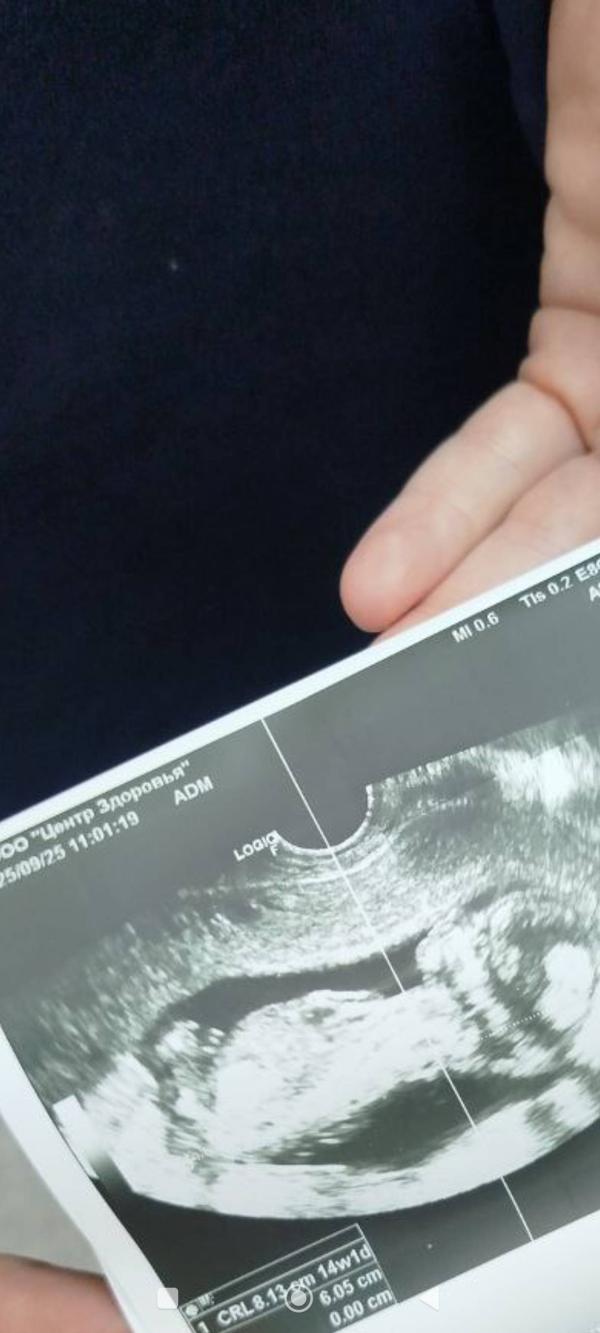

post image

Есть предположение девочка или мальчик? 🫣

Не видно полового бугорка тут

Мальчик 👦

Не разбираюсь, но чувствую что девочка